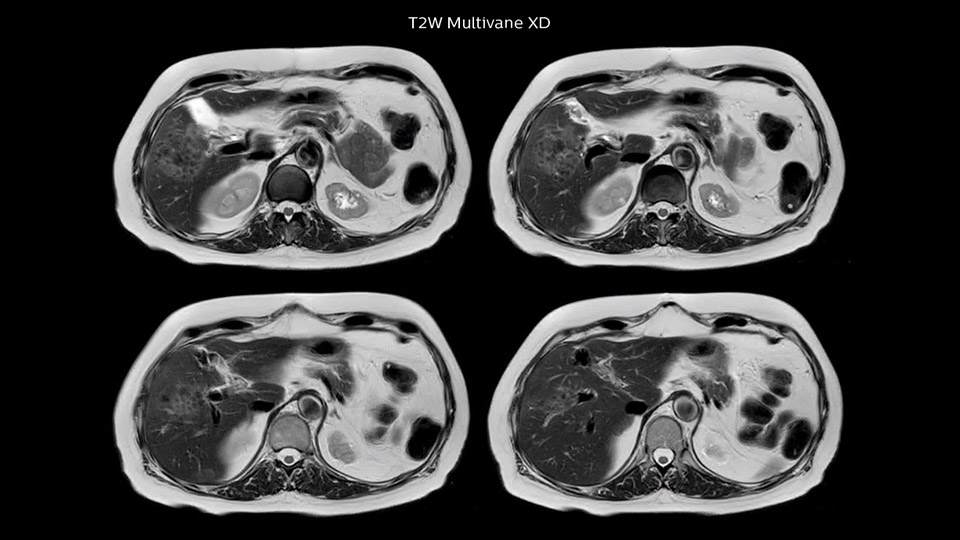

Dr. Baumann then implemented MultiVane XD for motion correction. It uses an extended reconstruction algorithm for imaging that is virtually motion free. “With MultiVane XD we get excellent motion-corrected images with high spatial resolution. We typically first optimize our scan for high image quality, and when satisfied with that, we try to reduce the scan time. So, we combined MultiVane XD with dS SENSE, which allows us to shorten the scan time,” he explains. “The performance of MultiVane XD in liver imaging is outstanding. MultiVane XD with dS SENSE is a powerful development in improving liver image quality.” “As we use breathhold imaging for T2-weighted liver scans, we depend on the patient’s ability to cooperate with the exam. This can present a real challenge when we are looking for small lesions, such as in our oncological patients. However, with MultiVane XD motion correction, we get excellent images. This is important for our surgeons, because they want to know exactly where the lesions are.”

In this example the image quality of the MultiVane XD images is evidently better than in the images without MultiVane XD. Ingenia 1.5T with dS Torso coil solution.

“Our liver exams are quite fast,” says Dr. Baumann. “If the patient tolerates it, we use an arms-up position to reduce the FOV and speed up the exam with dS SENSE.” “We acquire one transversal high resolution T2-weighted sequence with 3 mm slice thickness, for example for pancreas or liver lesions. Then we also add a T2 fat suppressed MultiVane XD SPIR sequence. We perform these two routinely in our liver imaging. We use high dS SENSE factors to significantly shorten scan times to 2-4 minutes, which can improve our protocol; it’s a very robust scan.” “We include mDIXON for the dynamic sequences because of the robust and homogeneous fat suppression we get with that. We had been using eTHRIVE, but we are now quite happy with mDIXON. Sometimes we use a medication to calm the bowels, to further improve the image quality.”

“I would absolutely recommend to other sites to implement MultiVane XD with dS SENSE in their abdominal cases, as it’s brilliant for robust, motion-corrected abdominal imaging. It provides us with excellent image quality with high resolution in a short time,” says Dr. Baumann. “I would advise using MultiVane XD for T2 and T2 fat suppressed high quality imaging for almost every liver case.”